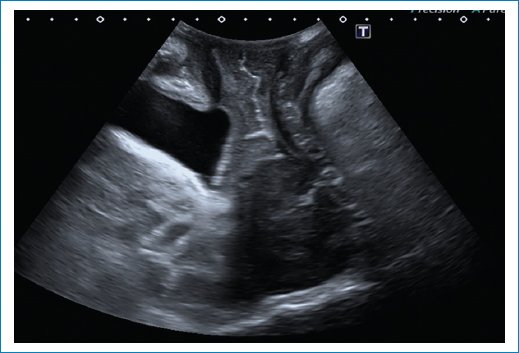

• – Rectocele con defecto de tabique rectovaginal (Fig. 15).

Figura 15. Se observa un rectocele anterior durante Valsalva.